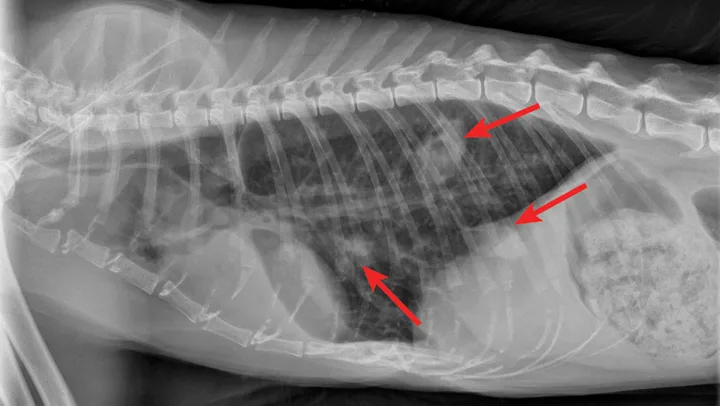

Radiographic evaluation is variable. Classic cranioventral distribution is less common in cats (Figure 3). A bronchial pattern is most common; however, bronchointerstitial, alveolar, and more structured pseudonodular patterns can occur.6,8 Occasionally, pulmonary abscesses may be appreciated and resemble pulmonary neoplasia (Figure 4).

FIGURE 4

Radiograph of pulmonary abscessation. The pulmonary nodules (arrows) could be mistaken for pulmonary neoplasia. The margins of these nodules are slightly less well demarcated than in neoplasia. Improvement was achieved with antibiotic therapy.